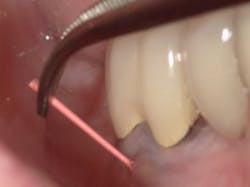

Most fistulas are endodontic or periodontal in nature. The appropriate specialist referral is possible with endodontic gutta percha (GP) points. As they appear radiopaque on x-rays, threading an open fistula can help confirm the origin of its source. Every office should have a vial of 30-gauge GP for this reason. First, break the point in half so that during an x-ray the patient does not accidentally bite down on it. Using cotton pliers, gently guide the point through the fistula until there’s resistance. A radiograph can then be used to determine the next course of action. Don’t be fooled and assume the source. Many times, a GP point will veer off in a surprising direction.

These same GP points can be used as a patient visual for probing depth. How many times have you probed an area of bone loss or potential fracture, only to have the patient respond, “But it’s not bothering me”? GP points can be directed into sulcus spaces and radiographed as a visual.